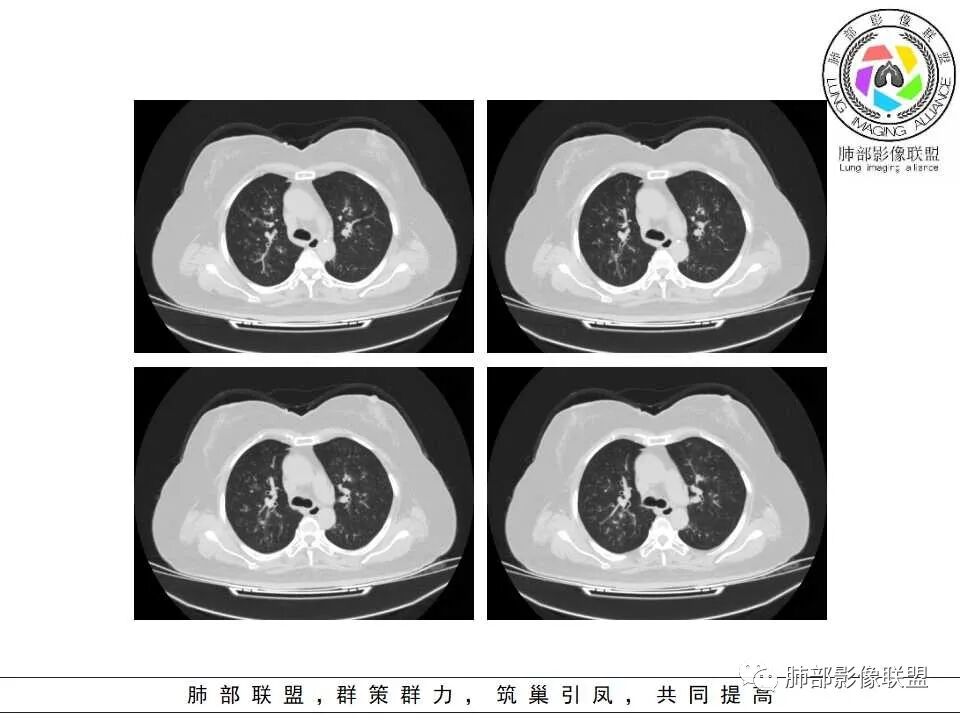

老年女性,发现白细胞升高两年,此次入院多次查外周血白细胞>30*10^9/L,淋巴降低,CRP显著升高,但病程中无发热,以细菌性炎不好解释;CT提示有脾大,结合外周血象,首先考虑存在血液系统疾病(白血病)基础,且未系统诊治;肺部CT提示双肺中轴间质增粗,伴随支气管管壁增厚?多发树丫及腺泡结节,部分呈点晕征,可见肺动脉分枝增粗,一元论考虑白血病肺部浸润;二院论考虑白血病并发气道侵袭曲霉。以患者病程进展看,更倾向于白血病肺部浸润。

1.病灶沿支气管分布的特点相当明显,相应支气管壁广泛增厚。这种与支气管关系极为密切的片影和/或结节影,常高度提示气道相关感染,如支气管肺炎。

2.患者两肺多发病变,具有广泛性。如此广泛分布更多见于免疫低下的机会性感染。

3.支气管壁广泛增厚对气道侵袭性曲霉病具有一定的提示意义。注意患者没有支气管扩张,临床也未提供IGE等实验室资料。

1.器官支气管管套样壁增厚和/或支气管扩张,注意壁增厚较均匀,和/或伴有播散性小片影及结节影,注意这些小片影或结节影边界有时较普通炎性病灶清楚。

1.多见于血液恶性肿瘤及造血干细胞移植患者。两肺多发,多见磨玻璃晕,有时病灶基底贴近胸壁形成楔形影。

2.很少支气管壁增厚,也无支气管扩张,少见树芽征。